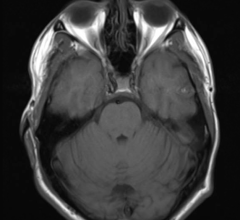

May 6, 2021 — Magnetic Resonance Imaging (MRI) images are usually meant to be static. But now, researchers from Mātai ...

May 5, 2021 — For patients with brain metastases, amino acid positron emission tomography (PET) can provide valuable ...